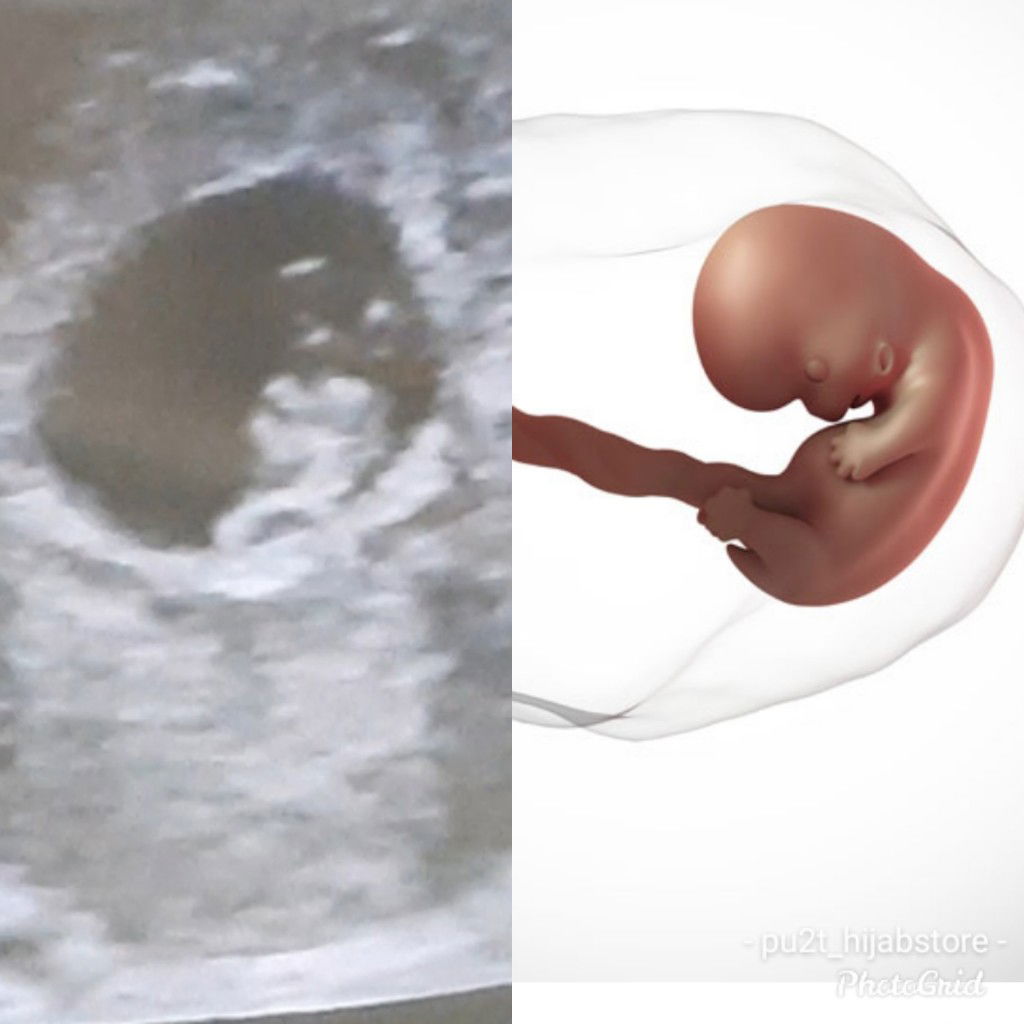

Bun mau tanya ada ga yg kaya saya stelah keguguran kmrn tgl 23 agustus pas saya iseng tespek tgl 6 novoktober allhamdulillah positif langsung pas saya k spog kandungan ku sudah berusia 7w6d .berarti saya ga kosong lg bun. Saran doktr dlu stlh kguguran kosong dlu 3 bulan tp saya gak kb. Saya antara senang dan takut beresiko .tp stlh periksa saya bahagia bgt soal y ddj sudah terdengar bayi y sehat .pdhl saya gatau klo hamil aktivitas sperti biasa mnum obt juga pk skincare dll